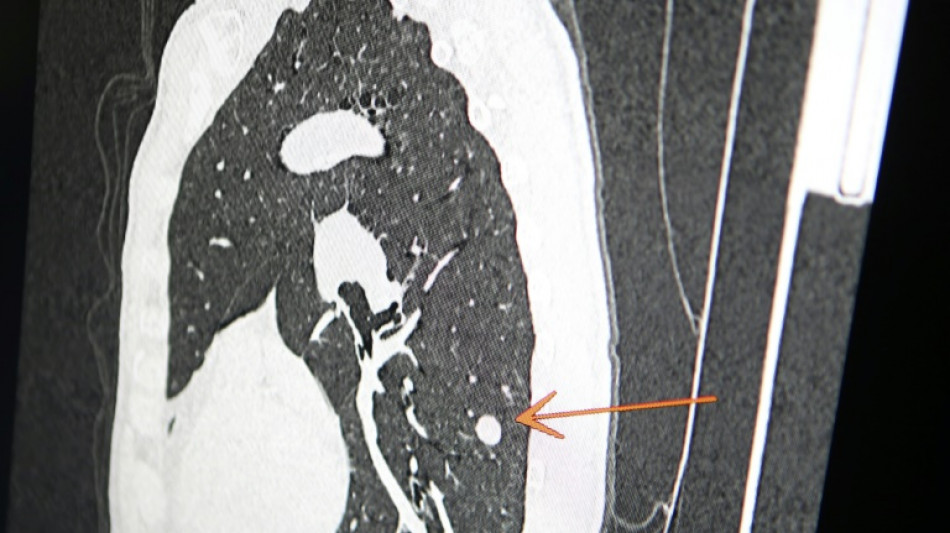

"Usted tiene cáncer", mensaje erróneo y aterrador a cientos de pacientes de una clínica en Inglaterra / Foto: Pascal Pochard-Casabianca - AFP/Archivos

Una clínica del norte de Inglaterra dio un gran susto a cientos de pacientes al enviar el mensaje "diagnóstico: cáncer de pulmón agresivo con metástasis" en lugar de sus buenos deseos de Navidad, informó el diario The Sun el jueves.

El 23 de diciembre a las 15H49, los pacientes de este centro de salud de Askern, cerca de la ciudad de Doncaster, recibieron un mensaje de texto en su teléfono informándoles de este diagnóstico, pidiéndoles que rellenaran los formularios correspondientes y concluyendo: "Gracias".

Según The Sun, entre los destinatarios del mensaje figuraba Chris Reed, un padre de familia de 57 años, que esperaba resultados de análisis para determinar si padecía cáncer de pulmón.